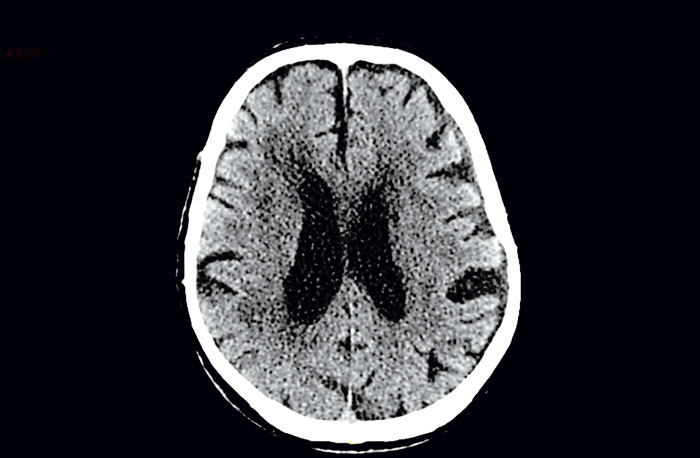

I trombolys- och heparinstudier av ischemisk stroke föreligger en hög frekvens av hemorragisk transformering av hjärninfarkten (Figur 2) [8, 9]. I ECASS 2, en RCT av vävnadsplasminogenaktivator (tPA) mot placebo, följde man patienterna med tre DT-undersökningar den första veckan. I placebogruppen fick 40 procent hemorragisk transformering, medan andelen i tPA-gruppen var 47 procent [8].

I en annan RCT där ASA jämfördes med LMWH gjordes kontroll-DT dag 10. Vid detta undersökningstillfälle sågs hemorragisk transformering hos 33 procent i ASA-gruppen och hos 36 procent i LMWH-gruppen [9]. Något lägre siffror sågs i den norska studien av ASA jämförd med LMWH: 14,2 respektive 11,6 procent [7]. Hemorragisk transformering är vanligare vid stor hjärninfarkt (än vid liten) och vid hjärninfarkt orsakad av kardiell embolisering eller storkärlssjuka (än vid småkärlssjuka) [9].

Hemorragisk transformering med neurologisk försämring, symtomgivande intracerebral hemorragi, ses oftare vid stor hjärninfarkt än vid liten. Behandling med tPA, i synnerhet i kombination med ASA, ökar också risken för symtomgivande intracerebral hemorragi. Andra faktorer kopplade till symtomgivande intracerebral hemorragi är högt blodtryck, hög ålder och hjärtsvikt [8]. Tyvärr saknas systematiska studier av risken för symtomgivande intracerebral hemorragi hos oselekterade grupper av patienter med akut ischemisk stroke och förmaksflimmer.

Svaret på frågan om hur stor risken för blödning är vid akut stroke blir att vi inte vet. Kontroll-DT ger oss möjlighet att upptäcka hemorragisk transformering men säger lite om risken för försämring vid insättning av antikoagulantia. Däremot kan definitionen av symtomgivande intracerebral hemorragi uppfyllas om patienten försämrats kliniskt och intrakraniellt hematom konstateras på DT.

Figur 2. 73-årig man med tidigare stroke och förmaksflimmer inkommer med nya strokesymtom. DT-hjärna visade nytillkommen occipital hjärninfarkt med hemorragisk transformering (ljusare partier mot mörkare bakgrund) och äldre frontal hjärninfarkt (jämfört med tidigare DT).